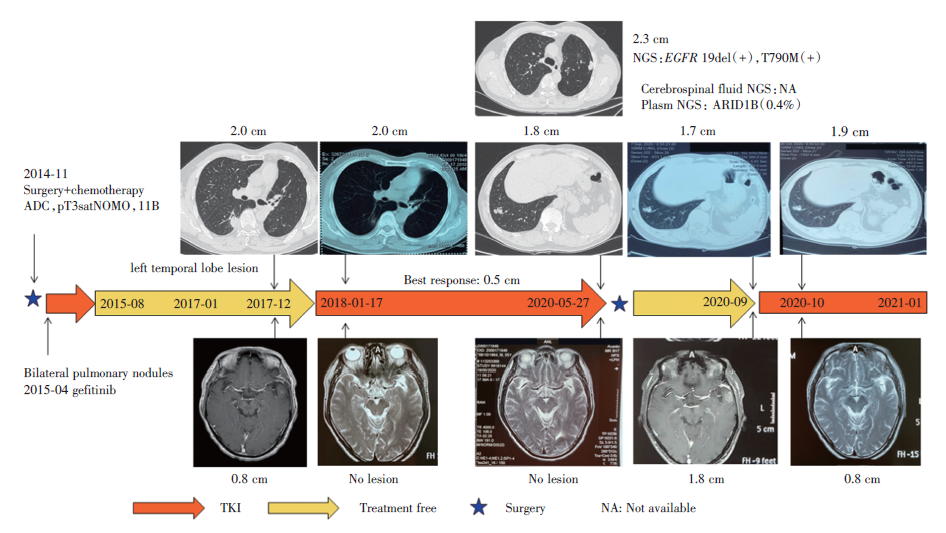

患者于2014年11月体检发现左上肺两个结节, 长径分别约2.5 cm及1.5 cm, 考虑肺恶性肿瘤, 未见纵隔淋巴结肿大及远处转移征象。2014-11-24于外院行左上肺切除术+纵隔淋巴结清扫术, 术后病理及分期:左上肺腺癌, pT3satN0M0, Ⅱ B期(按第八版分期), EGFR 19del(+)。术后行培美曲塞+卡铂辅助化疗4周期, 化疗后复查CT示双肺多发小结节影, 考虑转移。2015年4月开始口服吉非替尼。

患者于2015年8月来我院门诊, 复阅术前及术后CT, 对比发现双肺结节术前即已存在(术前CT, PET/CT均未报), 予停用吉非替尼。后续定期复查CT, 发现肺内结节逐渐增大。2017年1月行头颅MR提示左侧颞叶结节, 大小约0.7 cm, 考虑转移(见图1)。诊断:左上肺腺癌, cT4N0M1b(双肺、单发脑), Ⅳ A期。

按照MTD讨论意见, 虽然已发现颅内转移结节, 但肿瘤生长非常缓慢, 转移病灶不足1 cm, 遂予继续观察。2017-10-12复查CT及头颅MR提示肺内结节无变化, 左颞叶病灶约7 mm, 9个月观察随访没有变化, 继续随访不加干预。2017-12-12行CT提示新发右下肺结节, 大小约2.0 cm, 肺部其余结节无变化, 头颅MR提示左颞叶结节0.8 cm(见图2)。

患者于2017-12-22开始口服吉非替尼, 1个月后复查提示双肺结节及左颞叶病灶明显缩小(见图3), 疗效评价SD(-23%), 后续定期复查, 病灶继续缩小, 最佳疗效PR(-74%)。

2019-06-17复查CT示左下肺病灶增大, 疗效评价PD, 考虑缓慢进展, 继续口服吉非替尼。2020-05-27行CT示左下肺病灶较前增大, 约2.3 cm(见图4)。

患者于2020-06-01行左下肺楔形切除术, 病理提示为腺癌, 组织行NGS提示:EGFR19外显子缺失(19.2%)、T790M突变(13.5%)、CDC73突变(12.7%)、GNA11突变(10.5%)、HDAC2突变(12.4%); 血液NGS未见基因改变。予停用吉非替尼。

2020-09-07行头颅MR提示:原脑转移灶消失部位见转移瘤, 大小约1.8× 1.3 cm。2020-09-11行血NGS提示:ARID1B(0.4%)。脑脊液NGS无法检测。2020-09-21口服吉非替尼。2020-10-27复查头颅MR提示:脑转移病灶较前缩小, 约0.8 cm。

2021-01-22行CT示:双肺多发结节, 部分较前增大, 考虑转移。2021-01-23行头颅MR:左侧颞叶结节, 0.9 cm, 颅内多发点状影。患者诊治过程见图5。